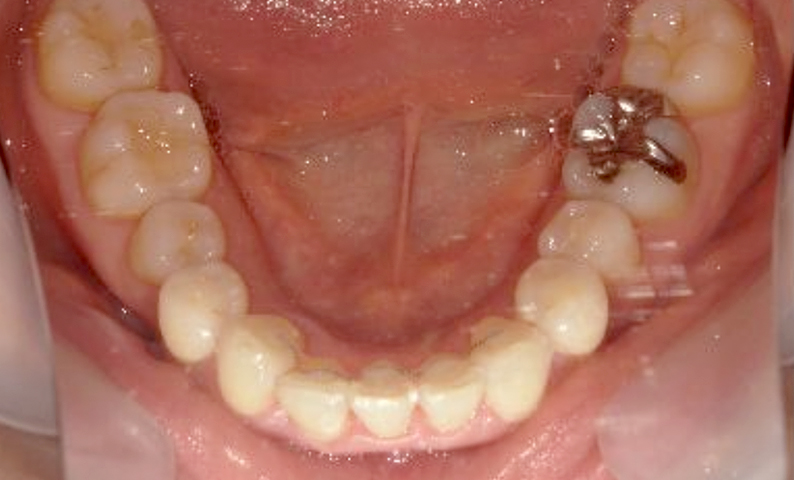

症例_003 下顎だけの部分矯正

治療期間:10ヶ月金額:24万円+税女性前歯のガタガタ下の前歯だけ上顎は補綴治療中

| Before | After |